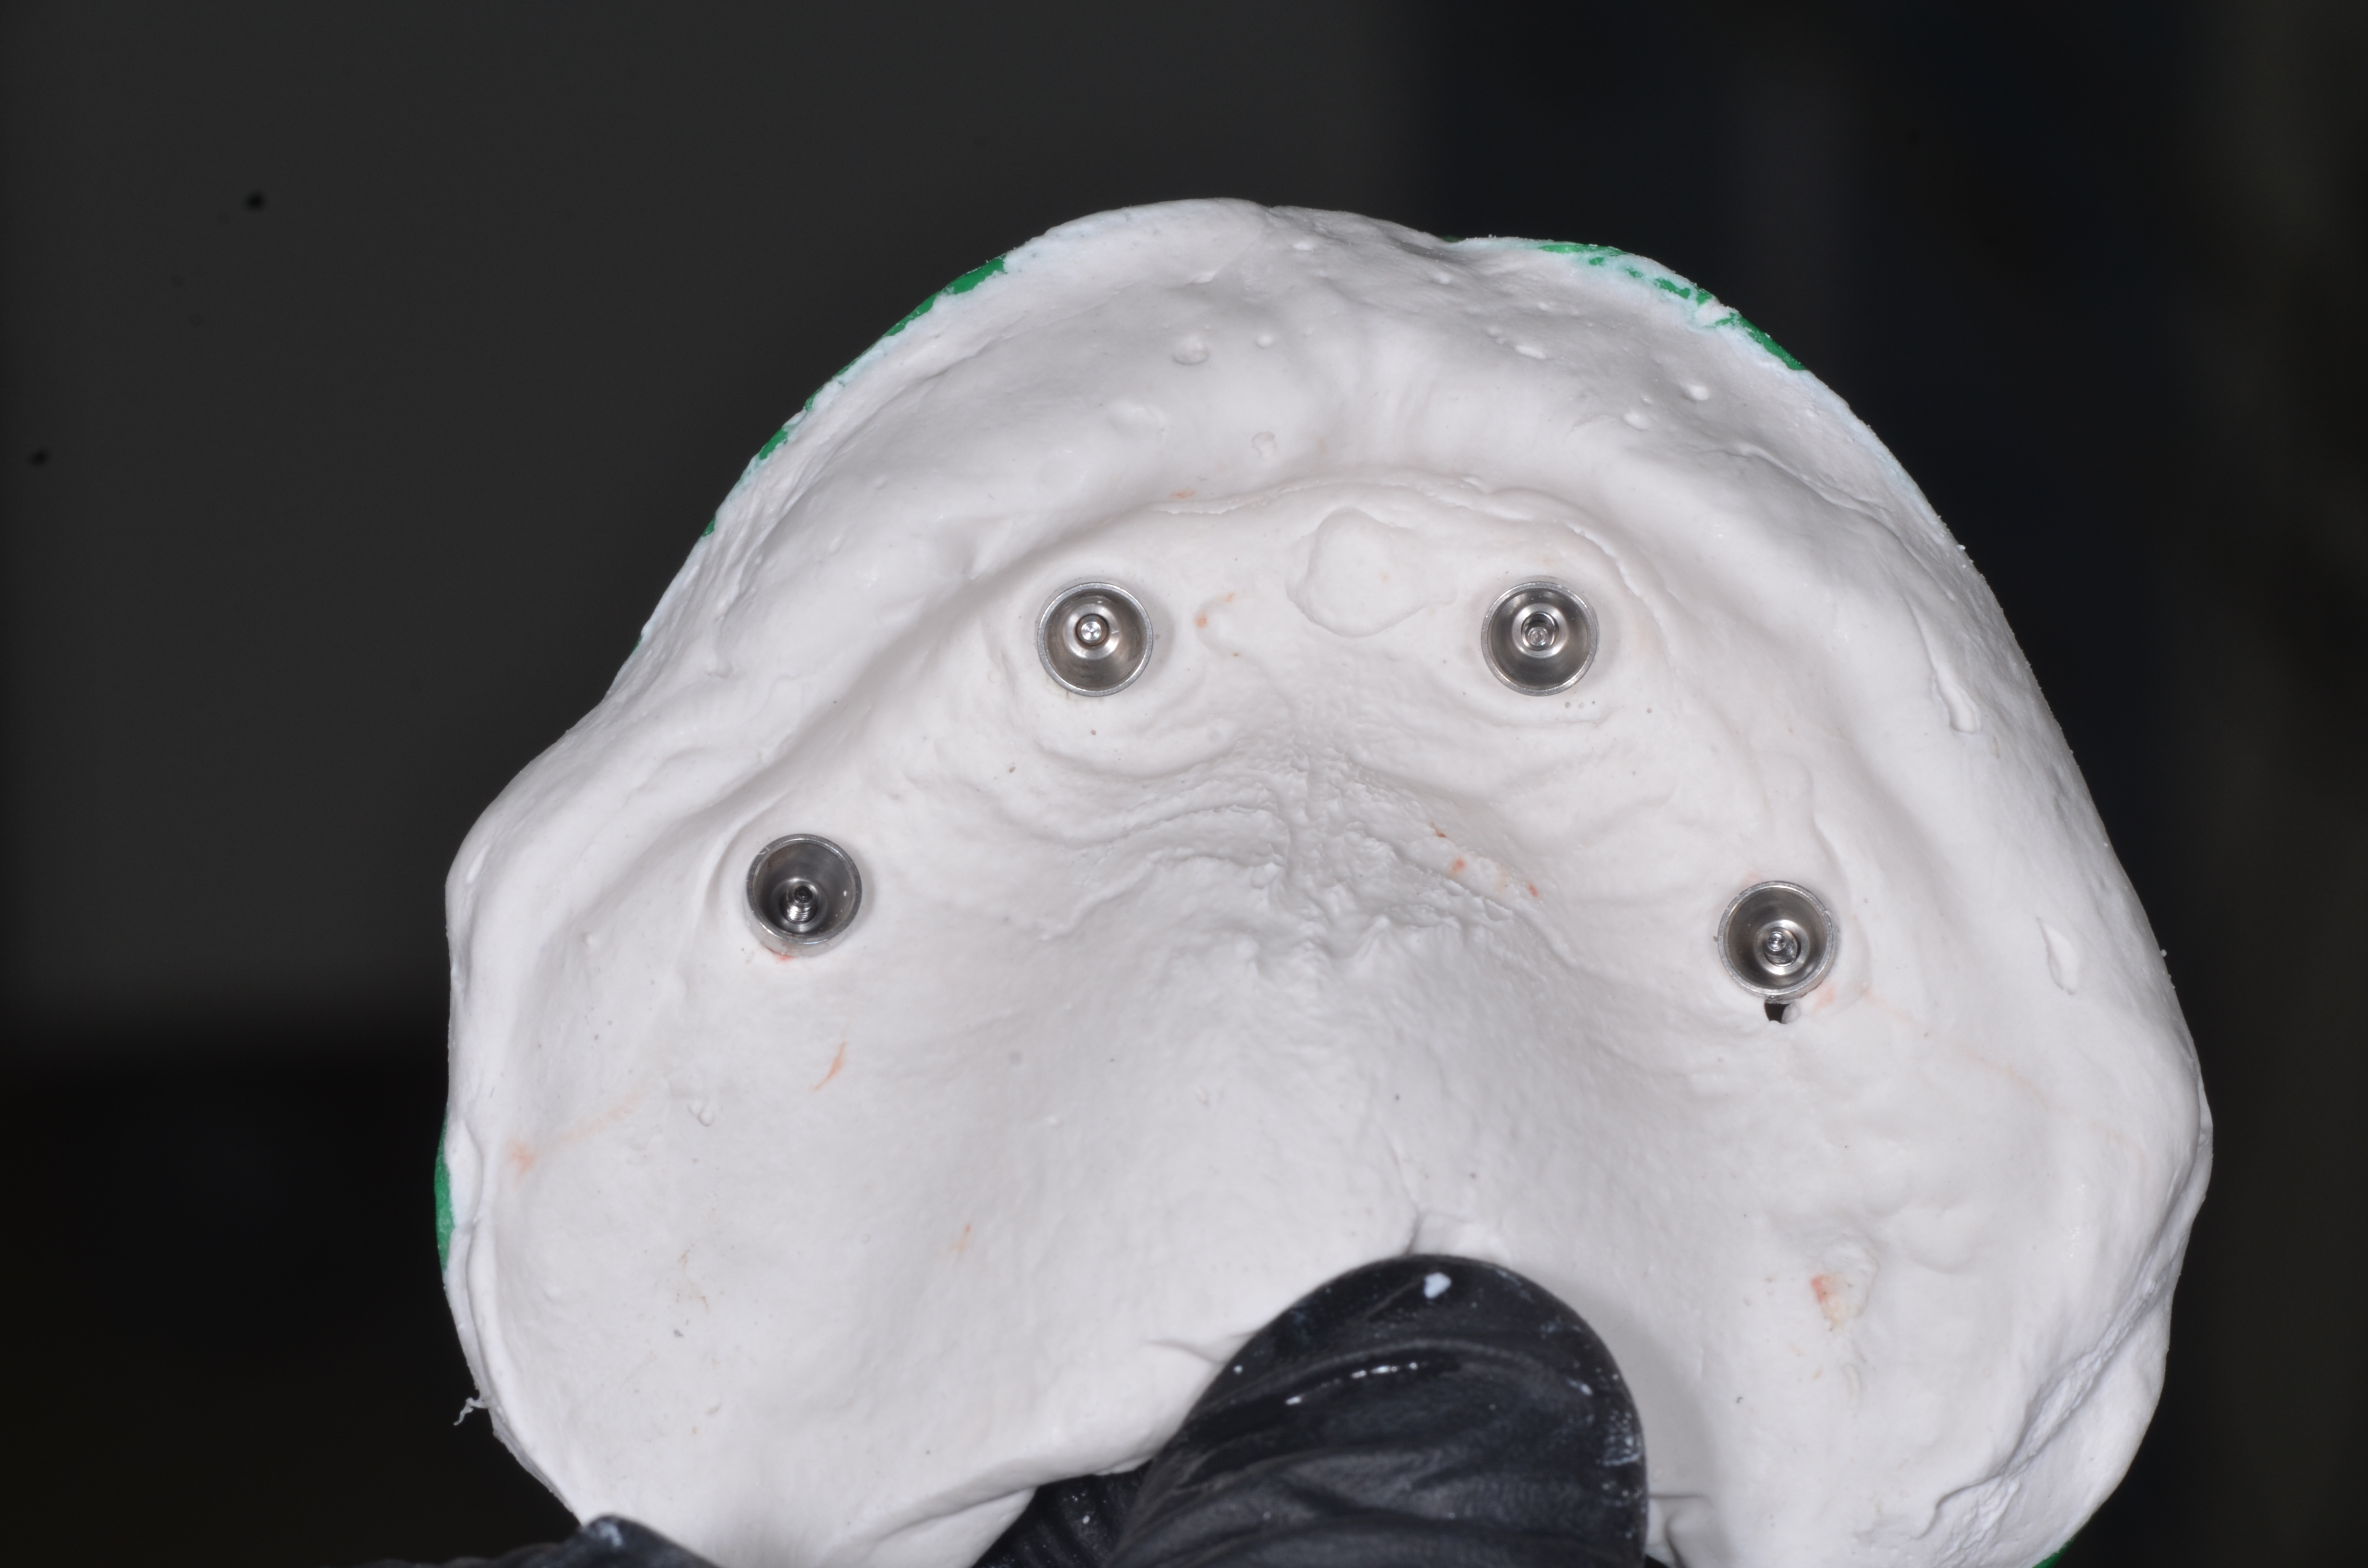

Зубной техник с протеза отливал модель с новыми десневыми контурами и положениями установленных имплантатов. После этого отделив титановые цилиндры от протеза зафиксировал их в модели к аналогам имплантатов.

Армирование протеза проводилось с помощью специальных титановых балок «TiRebar». Титановые балки с помощью композита фиксировались к титановым цилиндрам (рис. 33).

После полимеризации композита откручивались винты и проверялась пассивная посадка титановой балки к аналогам имплантата. Уже после этого зубной техник припасовывал акриловый протез к модели и перебазировал с пластмассой холодного отверждения на основе полиметилметакрилатов. После полимеризации протеза сошлифовали небную пластинку и излишки базиса с вестибулярной поверхности, при этом придесневая поверхность протеза оставалась относительно выпуклой или плоской , чтобы в дальнейшем не препятствовать осуществлению самостоятельной гигиене полости рта пациента (рис.34,35).